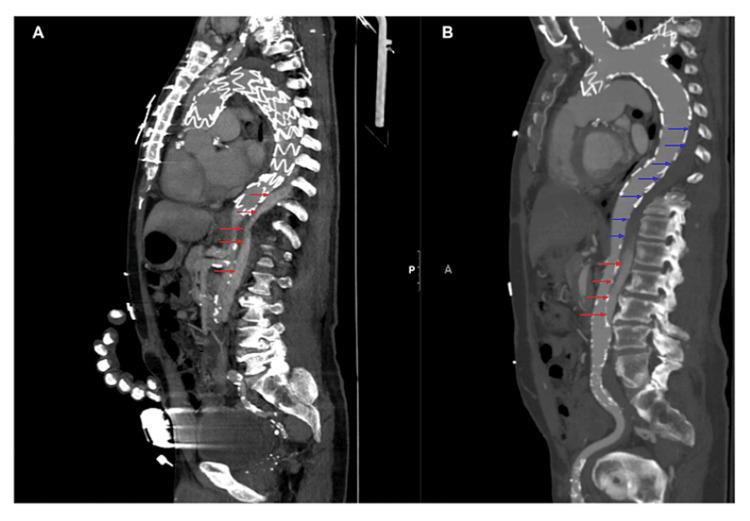

Spinal cord ischemia (SCI) is an uncommon but serious complication of thoracic endovascular aortic repair (TEVAR). SCI after TEVAR is thought to result from decreased segmental blood supply to an important network of collateral blood flow in the spinal cord. Little is known about the prevalence and optimal treatment of SCI that occurs beyond the periprocedural period. We report a case of delayed SCI in a 67-year-old patient who underwent TEVAR. The patient presented almost two years after TEVAR with acute paraplegia preceded by pre-syncope. The delayed SCI was likely triggered by pre-syncope, a thrombosed endoleak shown on imaging, and the patient's vascular risk factors. Treatments included cerebrospinal fluid (CSF) drainage, mean arterial pressure (MAP) augmentation, and a naloxone infusion, which resulted in moderate recovery in lower extremity motor function. This case highlights the tenuous nature of spinal cord perfusion after TEVAR and that prompt recognition and early treatment of SCI are critical in preventing the progression from ischemia to infarction.

脊髓缺血(SCI)是胸段血管腔内主动脉修复术(TEVAR)一种罕见但严重的并发症。TEVAR术后的SCI被认为是由于脊髓重要侧支血流网络的节段性供血减少所致。对于围手术期之外发生的SCI的患病率和最佳治疗方法知之甚少。我们报告了一例67岁接受TEVAR手术患者发生迟发性SCI的病例。该患者在TEVAR术后近两年出现急性截瘫,之前有晕厥前症状。迟发性SCI可能是由晕厥前症状、影像学显示的血栓性内漏以及患者的血管危险因素引发的。治疗措施包括脑脊液(CSF)引流、平均动脉压(MAP)升高以及纳洛酮输注,这些措施使下肢运动功能得到了中度恢复。该病例突出了TEVAR术后脊髓灌注的脆弱性,以及对SCI的及时识别和早期治疗对于防止从缺血发展为梗死至关重要。